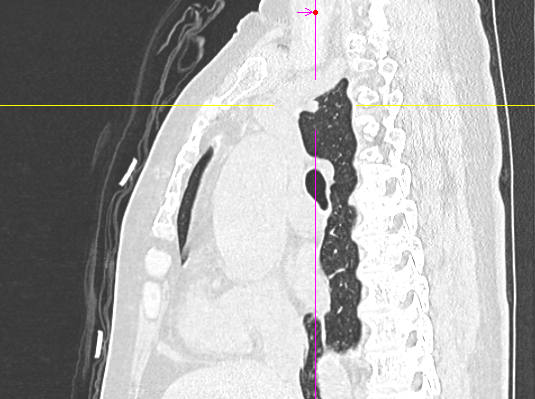

数月前,66岁的龚女士在肺癌术后随访复查中,胸部CT报告显示其右上肺新发实性结节一枚,并由刚开始发现时的5mm逐步增大至10mm。更棘手的是,这个结节位于右肺上叶尖段的纵隔胸膜下,位置极其“刁钻”。面对这份报告,患者龚女士陷入了深深的焦虑。因为其7年前因右中肺肿瘤行右中肺癌根治术,对于新发的实性结节为何种性质,是新发肺恶性肿瘤或是良性病变,亦或是原肺癌复发转移,目前均不能明确。辗转多家医院,得到的建议多为“定期观察,等待变化”或考虑创伤较大的传统穿刺活检,但结节位置非常深,单纯CT引导下定位穿刺很难精准到达,且需穿行的肺组织较多,创伤较大。

定位完成后,手术进入第二阶段。团队并未在患者胸部留下多个孔洞,而是仅在其肋间开创了一个长约3厘米的单一操作孔。通过这个“钥匙孔”,高清荧光胸腔镜顺利进入。在之前定位的明确指引下,手术团队迅速而准确地找到了这个深藏不露的结节,精准实施了“肺叶部分切除术”。

术中冰冻病理检查结果表示:(右上肺)结节见实性异型细胞巢,低分化癌首先考虑,结合临床病史,不排除为肺腺癌复发可能。由于患者既往行右中肺叶切除术且本次结节较小考虑复发转移可能,相关病情与家属沟通后确认不再扩大切除,本次手术及时处理、干预精准,明确病理,为患者后续治疗方案提供了指导方针。本次手术尽可能地保住了患者宝贵的健康肺功能。得益于超微创特性与科室成熟的ERAS(加速康复外科)流程,龚女士术后苏醒平稳,疼痛感轻微,术后第二天即可在家属搀扶下下床行走,康复速度远超预期。